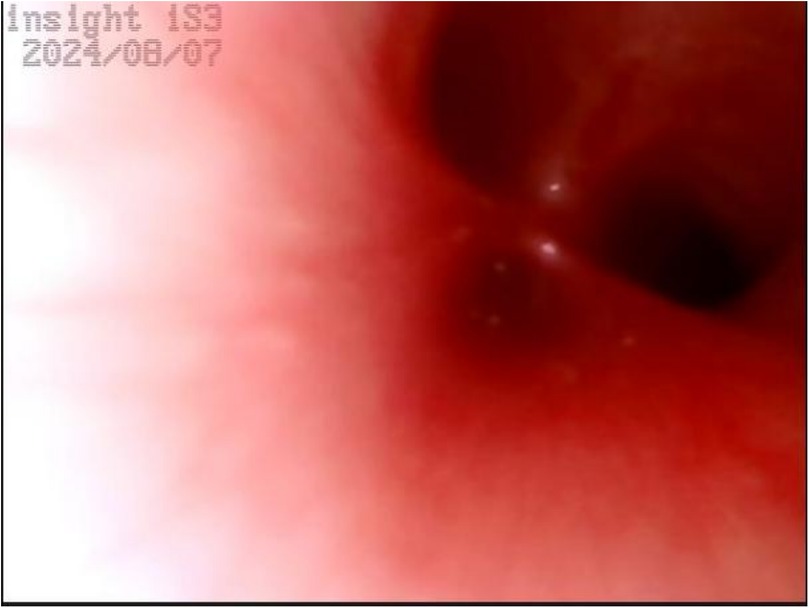

Upper gastrointestinal examination with iodinated water contrast revealed a cystic mass shadow at the level of the lower margin of the third thoracic vertebra (Figure 2). Congenital esophageal atresia (Type C) was suspected based on CT imaging of esophagus. Electron bronchoscopy visualized congenital esophageal atresia with a tracheoesophageal fistula (Figure 3). Craniocerebral ultrasound detected a subventricular cystic lesion on the left side and bilateral dilation of the lateral ventricles. Abdominal color Doppler ultrasound indicated hepatomegaly, with no apparent abnormalities in the gallbladder, pancreas, spleen, or kidneys. Cardiac ultrasound identified an atrial septal defect, patent ductus arteriosus, and patent foramen ovale. Amplitude EEG demonstrated immature sleep-wake cycles (SWCs). Hearing screening using Otoacoustic emissions and the auditory brainstem indicated abnormal results. Fundoscopic examination revealed congenital focal retinal choroidal defects in both eyes (Figure 4). Genetic testing with whole-exome sequencing was positive and identified a de novo heterozygous pathogenic variant in the CHD7 gene, confirmed by Sanger sequencing, with both parents being wild type at this locus (Supplementary Figures S1).

Figure 3. Electron bronchoscopy. At the level of the tracheal carina, an opening of a fistula is visible, with a diameter smaller than that of the left and right main bronchi. There is no swelling, and a small amount of white secretions can be observed.